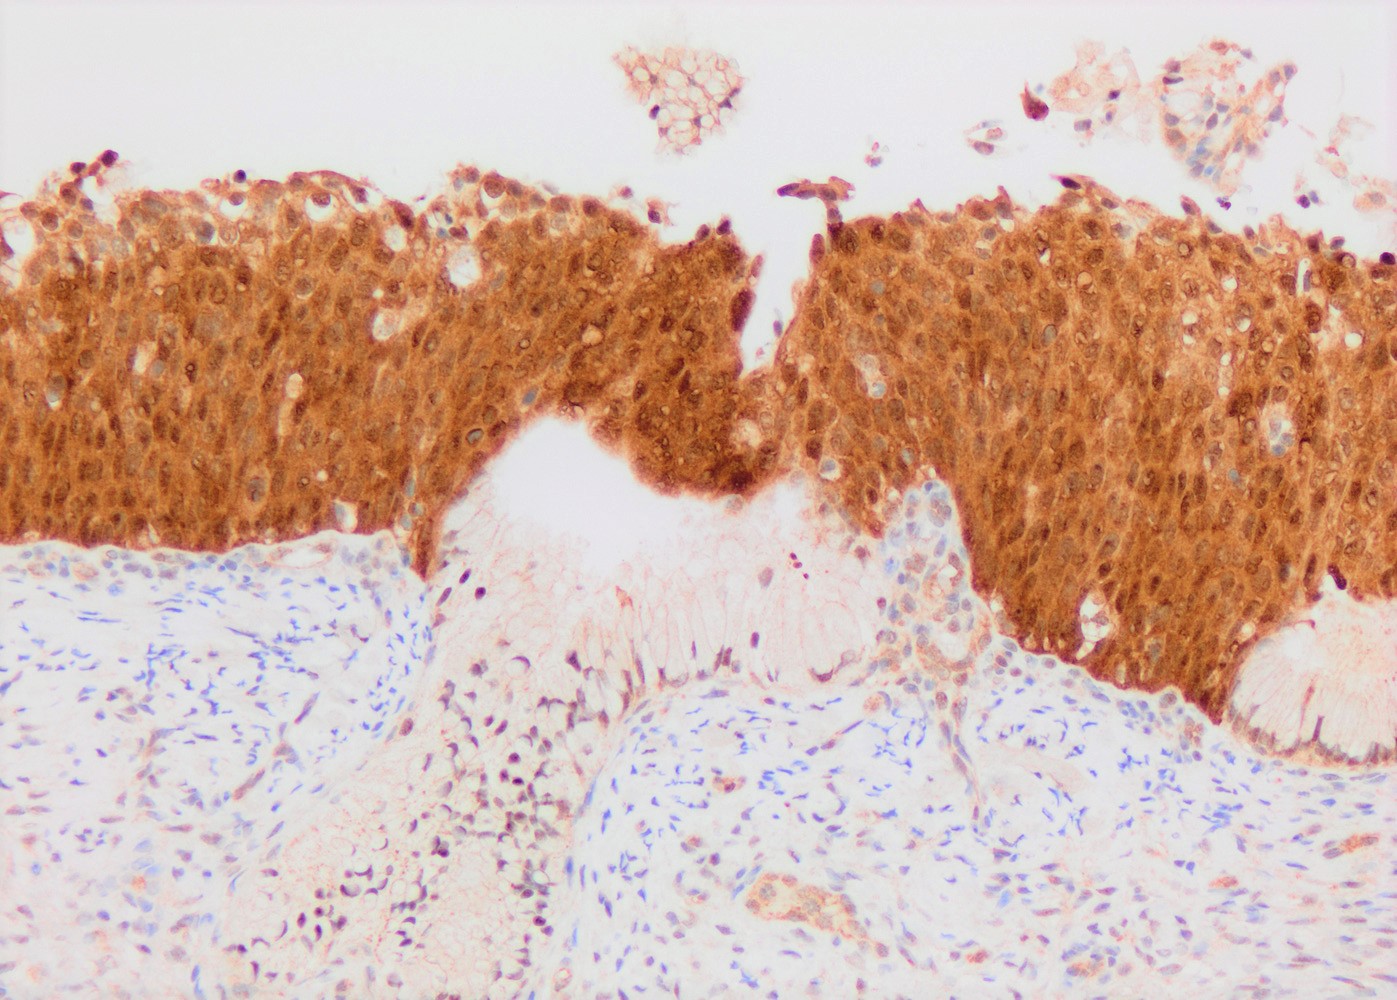

- p16: strong and diffuse block staining, continuous nuclear or nuclear and cytoplasmic staining in the basal layer of dysplastic epithelium with upward extension involving at least one - third of the epithelium; extension into the upper half of epithelium is not required

- Lower anogenital squamous terminology (LAST) project recommends p16 IHC in the following contexts (Arch Pathol Lab Med 2012;136:1266):

- Distinguish HSIL from mimickers (e.g. atrophy, immature metaplasia)

- Distinguish morphologically equivocal LSIL / CIN I versus CIN II

- Professional disagreement on diagnosis when HSIL is in consideration

- Biopsies showing ≤ LSIL in patients at high risk for missed HSIL based on prior Pap / HPV testing results

- Improper use of p16 IHC may lead to overdiagnosis of HSIL (Hum Pathol 2016;55:51)

- Lower anogenital squamous terminology (LAST) project recommends p16 IHC in the following contexts (Arch Pathol Lab Med 2012;136:1266):